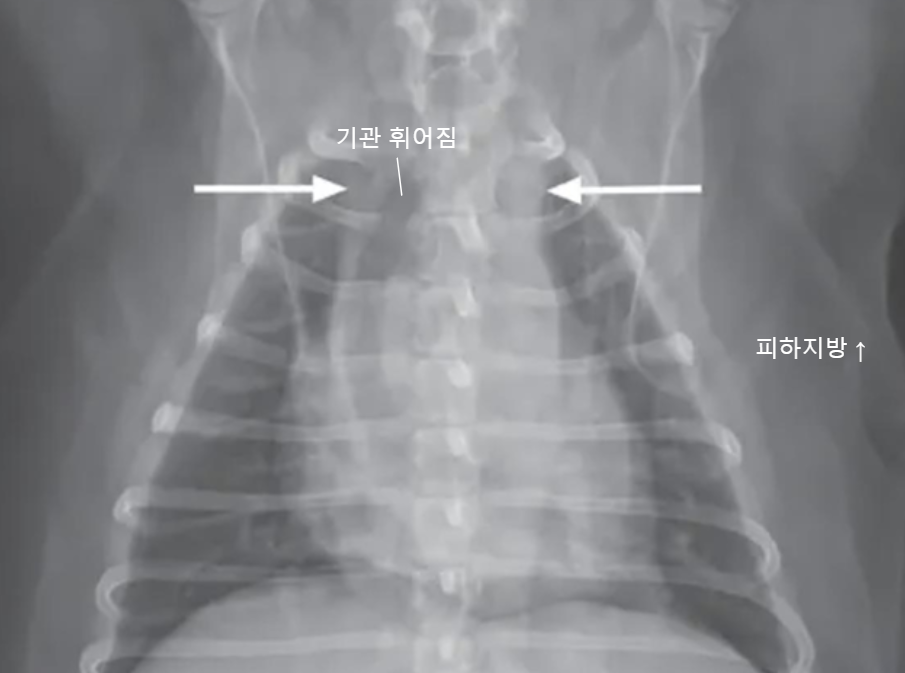

![]() | * 종격동의 정상 크기 - 척추뼈의 2배 정도 공간 - 고양이는 더 홀쭉함 |

![]() | - 종격동이 2배 이상 커지고, 기관이 휘어졌는데.. - 종양 때문일 수도 있지만, - 이건 살이 너무 많이 쪄서.. |